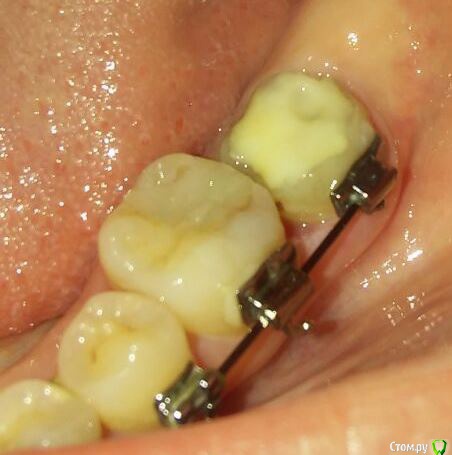

catalystka Опубликовано 19 мая, 2017 Поделиться Опубликовано 19 мая, 2017 Добрый день! У меня несколько месяцев назад образовался десневый карман между 6-м и 7-м зубом на нижней челюсти (ношу брекеты). Терапевт сделала чистку (кюретаж?). Через 2 недели после процедуры воспаление десны прошло, но она оставалась избыточной. Я обратилась к другому врачу, хирургу, который сделал коагуляцию десневого сосочка. На фото состояние через неделю после этого. Дырка в десне. Зря коагулировали? Десна могла опуститься сама? Как теперь поступить? Спасибо. Ссылка на комментарий

catalystka Опубликовано 19 мая, 2017 Автор Поделиться Опубликовано 19 мая, 2017 Спасибо за ответ. Исходного фото нет, к сожалению. Если объяснять на пальцах, во время приема пищи этот кусок десны отгибался вертикально в сторону дуги, и в этот треугольник забивалась еда.. А каковы возможные сценарии? Этот треугольник может зарасти? Его площадь наоборот увеличивается. В каком случае (и через какое время) идти ко врачу? Не хочется облажаться еще раз. Ссылка на комментарий